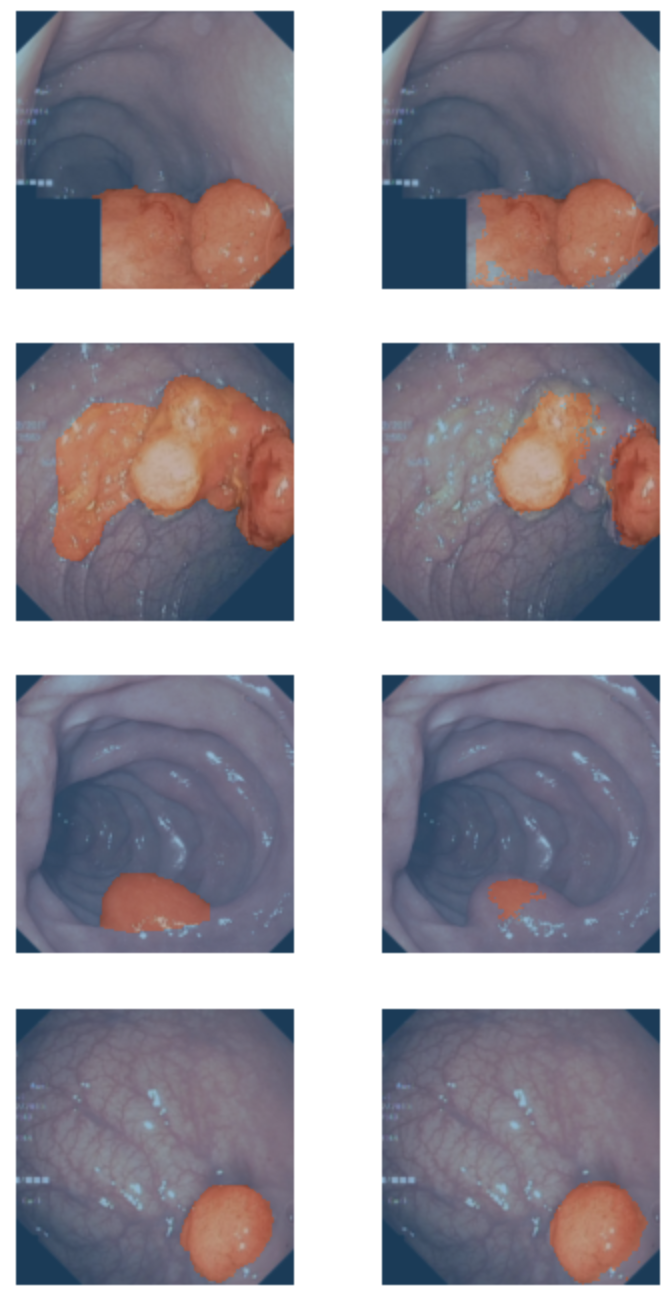

Results

Visualization of results

Target/Prediction